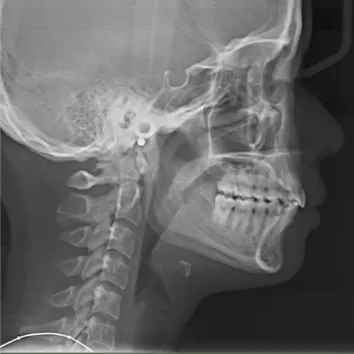

Rayons X avant le traitement

[Radiographie panoramique/Céphalogramme latéral]